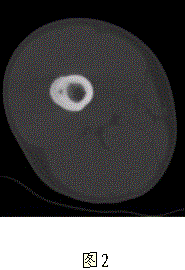

问题 患者男,17岁,右大腿外侧间歇性疼痛逐渐加重近3个月,夜间为重,X线片及CT示右股骨干下段外侧骨皮质梭形增厚硬化,增厚的骨皮质中心隐约可见小圆形低密度灶,骨髓腔未闭合,无外伤史(图1、2)。 最可能的诊断是

选项 A.成骨细胞瘤 B.骨软骨瘤 C.骨样骨瘤 D.骨肉瘤 E.非骨化性纤维瘤

答案 C